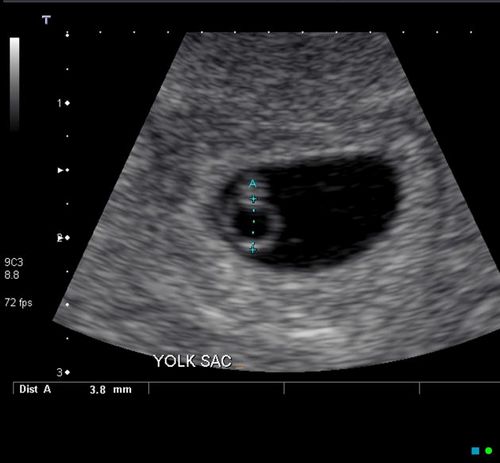

На третьому тижні після зачаття, тобто на п'ятій акушерської тижня, плодове яйце досягає величини 0,6-1,0 см. Усередині нього з'являється жовтковий мішок, необхідний для живлення ембріона. На цьому терміні плодове яйце зростає в діаметрі приблизно на 1 - 2 мм кожен день і візуалізується в проекції утолщенного ендометрія.

Жовтковий мішок візуалізується в матковій порожнини в першому триместрі (всього кілька тижнів від зачаття)

В середині п'ятого тижня від останньої менстру-ації (на третій з половиною тижні ембріонального віку) ембріончік розмірами 2 - 5 мм розташовуватись-ється поруч з жовтковим мішком, який візу-алізіруется як кругле утворення з прозорим вмістом. Розміри жовтковиммішка більше 6 мм або менше 2 мм можуть побічно говорити про загибель ембріона. Зображення нормального зародка з жовтковим мішком схоже на «подвійної-ної бульбашка».